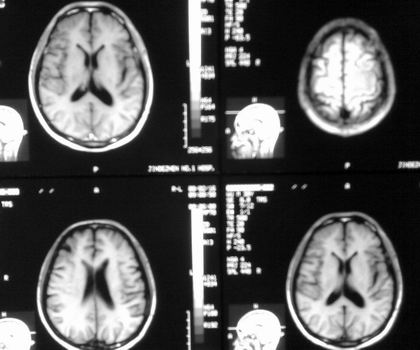

以下是引用杀毒软件在2008-2-17 14:43:00的发言:[br]左顶叶见片状低密度影,内见点状影,占位效应不明显。[br]左顶叶结核性肉芽肿可能性大。脑囊虫病?做补体结合试验除外。

以下是引用dyqct在2008-2-17 17:19:00的发言:[br][quote]以下是引用杀毒软件在2008-2-17 14:43:00的发言:[br]左顶叶见片状低密度影,内见点状影,占位效应不明显。[br]左顶叶结核性肉芽肿可能性大。脑囊虫病?做补体结合试验除外。[/quote[br]支持!!